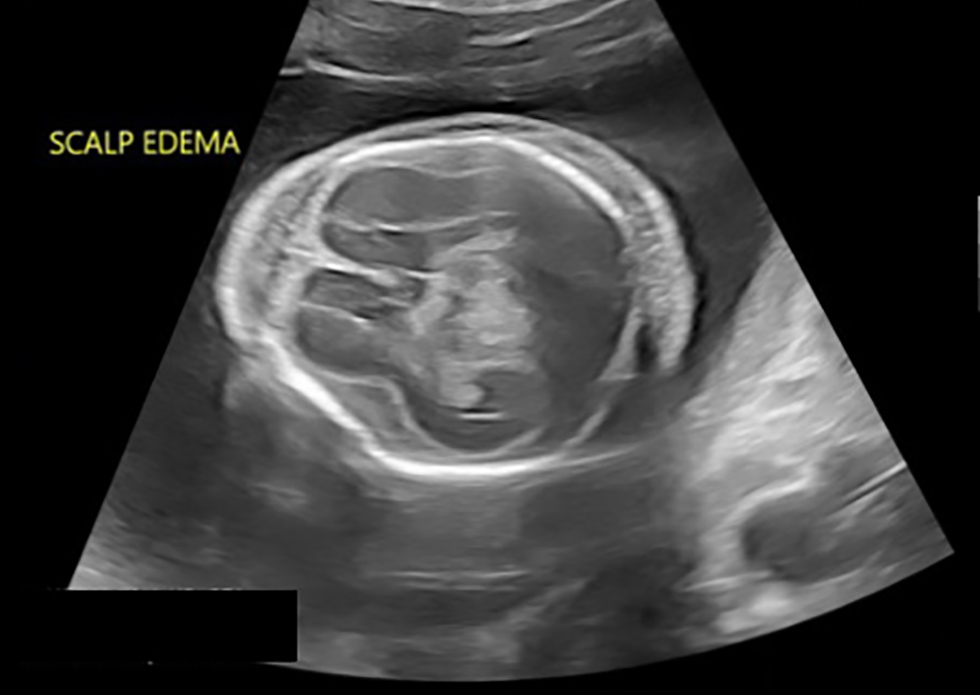

Ultrasound performed by Maternal Fetal Medicine demonstrated a single live intrauterine pregnancy at gestational age of 19+3 weeks. The fetus was affected by severe hydrops fetalis, as demonstrated by large pleural effusions, large ascites compressing the kidneys and body wall edema (Figure 1). The brain was very abnormal with bright cerebrospinal fluid and streaky echoes throughout the cortex (Figure 2). There was polyhydramnios with a maximum vertical pocket of 8 cm, with a thickened and overtly hydropic placenta (Figure 3). The umbilical artery Doppler ultrasound was abnormal with an increased systolic to diastolic ratio; however, the middle cerebral artery (MCA) Doppler did not demonstrate evidence of fetal anemia (peak systolic velocity 1.37 MoM). To complete the evaluation for hydrops, amniocentesis was performed and sent for microbiologic and genetic evaluation. Results are summarized in Table 2 and were notably positive for T. pallidum on PCR testing.

Figure 2: Marked scalp edema, very abnormal brain with bright cerebrospinal fluid, streaky echoes throughout brain matter at 19+3 weeks gestational age

Text description: Figure 2

Ultrasound image, taken a gestational age of 19+3 weeks. Cross-sectional view of skull, at the level of the cavum septum pellucidum. Notable is the marked scalp edema and very abnormal appearing brain matter with streaky echoes throughout and bright cerebrospinal fluid.